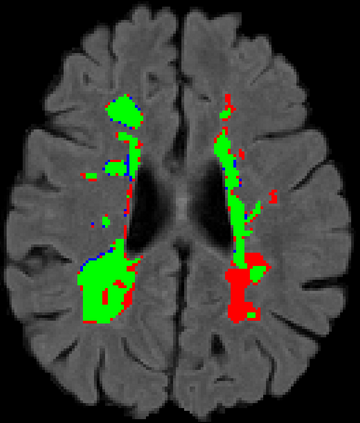

Recently, segmentation methods based on Convolutional Neural Networks (CNNs) showed promising performance in automatic Multiple Sclerosis (MS) lesions segmentation. These techniques have even outperformed human experts in controlled evaluation conditions such as Longitudinal MS Lesion Segmentation Challenge (ISBI Challenge). However state-of-the-art approaches trained to perform well on highly-controlled datasets fail to generalize on clinical data from unseen datasets. Instead of proposing another improvement of the segmentation accuracy, we propose a novel method robust to domain shift and performing well on unseen datasets, called DeepLesionBrain (DLB). This generalization property results from three main contributions. First, DLB is based on a large group of compact 3D CNNs. This spatially distributed strategy ensures a robust prediction despite the risk of generalization failure of some individual networks. Second, DLB includes a new image quality data augmentation to reduce dependency to training data specificity (e.g., acquisition protocol). Finally, to learn a more generalizable representation of MS lesions, we propose a hierarchical specialization learning (HSL). HSL is performed by pre-training a generic network over the whole brain, before using its weights as initialization to locally specialized networks. By this end, DLB learns both generic features extracted at global image level and specific features extracted at local image level. DLB generalization was validated in cross-dataset experiments on MSSEG'16, ISBI challenge, and in-house datasets. During experiments, DLB showed higher segmentation accuracy, better segmentation consistency and greater generalization performance compared to state-of-the-art methods. Therefore, DLB offers a robust framework well-suited for clinical practice.